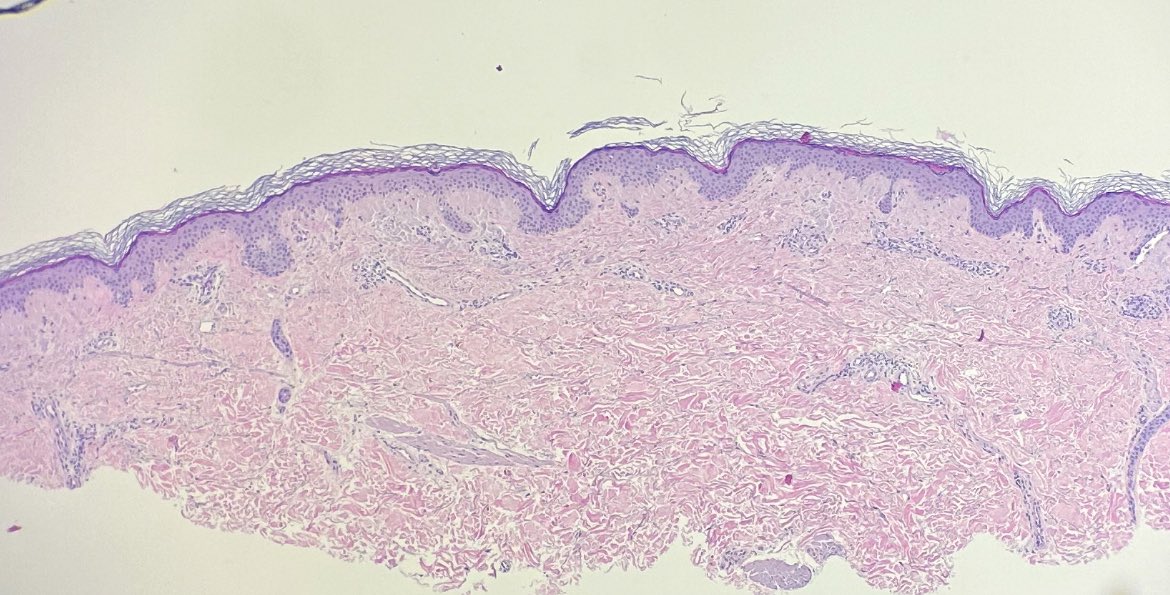

#dermpath for trainees. Middle aged adult, elbow. “Ddx dermatitis vs psoriasis” What is your low-power impression? Can we exclude psoriasis already?

I believe we can. Now, let’s look on high-power. What’s going on? How would you describe the papillary dermis? What’s your ddx and which stain(s) should you get?

So to recap: this is (macular) localized cutaneous amyloidosis. Presents as (usually) pruritic hyperpigmented macules/patches, usually on upper body/extremities. Amyloid is keratin-derived. Amorphous eosinophilic deposits + (some)🐷 incontinence.